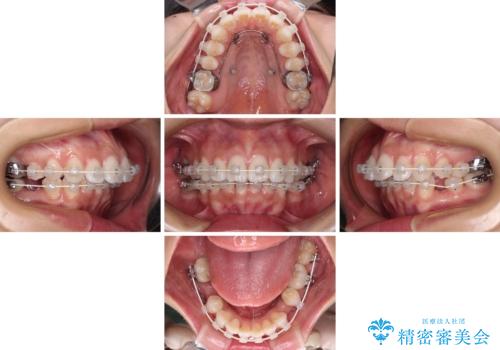

- 矯正装置

- 審美装置

- 治療期間

- 3年8ヶ月

- 治療回数

- 30回以上